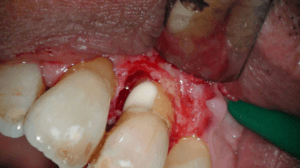

Na anesthesie volgde een flapoperatie om de pocket te openen. Al snel werd een breuk zichtbaar in het element. Maar hoe ver liep de barst door?

Voorzichtig verwijderden we alle granulatieweefsel en spoelden we het schoon. Wat we zagen had ik nog nooit eerder waargenomen. Er zat een min of meer circulaire barst wat eigenlijk een los zittend stukje dentine was.